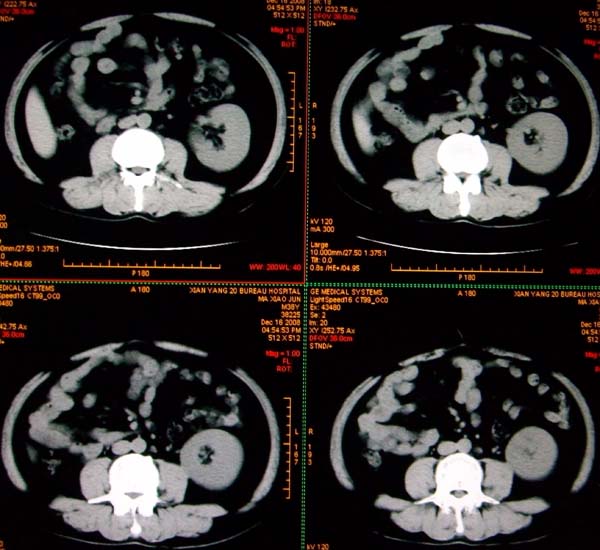

标题: CT17174:M38Y,体检超声提示右肾发育不良,病人无明显不适 [打印本页]

标题: CT17174:M38Y,体检超声提示右肾发育不良,病人无明显不适

右肾发育不良;考虑左肾下极血管平滑肌脂肪瘤可能,建议增强。

1)左肾下极占位性病变,不排除肾癌可能;建议行进一步检查。2)右肾发育不良。

左肾下极占位性病变,不排除肾癌可能;建议增强及明确内部组织ct值。右肾发育不良。

右肾发育不良。左肾下极占位。

右肾发育不良。左肾代偿。左肾下极占位,性质待定,建议强化。

右肾发育不良。左肾下极占位。建议增强!

右肾发育不良。左肾下极占位。  强化

右肾发育不良。左肾下极囊实性占位,建议增强。